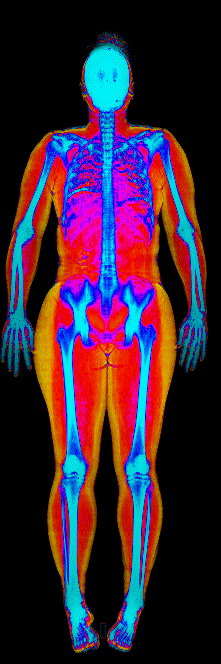

What Muscle Gain Looks Like on a DEXA Scan

Gained 21.7 lb lean · 158 → 184 lb · Age 31

Gained 12.1 lb lean, lost 9.2 lb fat · 188 → 191 lb · Age 27

Gained 9.2 lb lean, lost 6.6 lb fat · 173 → 176 lb · Age 33